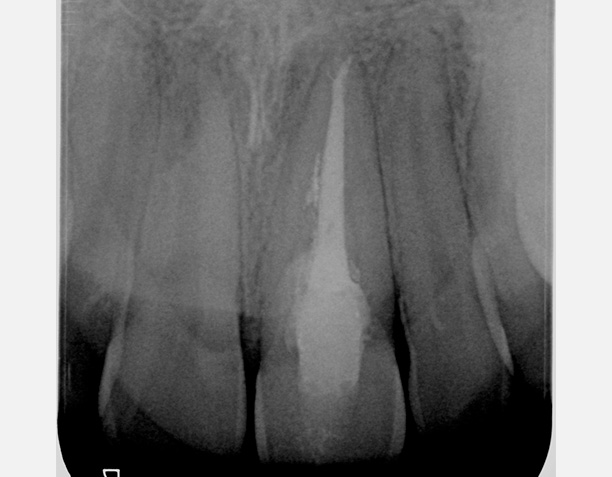

• Traitement endodontique : Sous anesthésie locale et à travers la protection d’un champ opératoire nous accédons à la pulpe de la dent à soigner, puis aux canaux de ses racines que nous devons désinfecter. Ce soin nécessite l’élimination complète de la source de contamination (souvent la carie) parfois sous une ancienne reconstitution ou une couronne qu’il faut alors retirer. Une fois le nettoyage et la mise en forme des canaux réalisés, nous les obturons de façon hermétique avec un ciment et un matériau thermoplastique appelé Gutta Percha. Ceci afin d’empêcher une nouvelle prolifération bactérienne et d’assurer le maintien de la dent dans ses structures de soutien (ligament parodontal et os alvéolaire). L’ouverture effectuée au centre de la dent sera d’abord refermée avec un pansement provisoire avant d’envisager ensemble la reconstitution d’usage : un composite, un inlay-onlay ou une couronne.

Avant